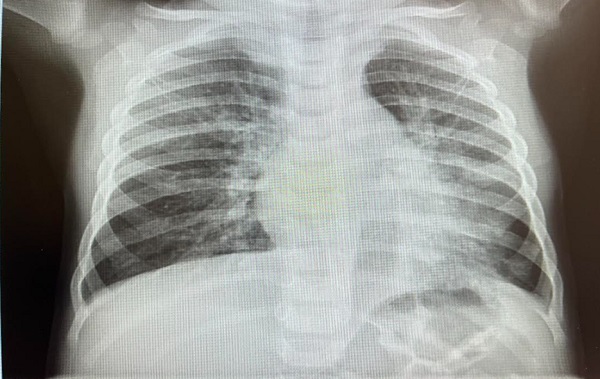

Se observa que en un episodio de noviembre del 2022 presenta una infección respiratoria con patrón radiográfico de neumonía atelectasia de LII (Figura 2).

Figura 2. Neumonía atelectasia de LII